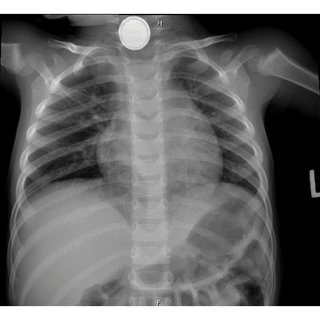

2: 버튼 배터리

• 이 중 버튼 배터리는 삼킨 지 3~4시간 내 식도 전 층에 화상을 유발할 수 있어 최대한 빨리 내시경적으로 제거해야 한다.